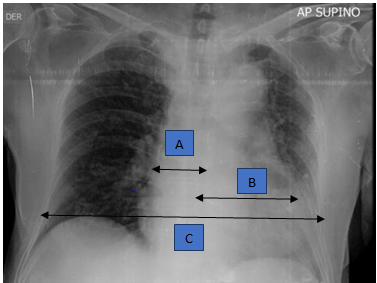

The portable chest X-ray was interpreted with a cardiothoracic index (A+B/C) greater than 2, associated with effacement of the aortic knob and alveolar opacities of parahilar distribution, in the context of signs of postcapillary pulmonary hypertension (Figure 1).

Figure 1 Anteroposterior projection (AP) chest X-ray.